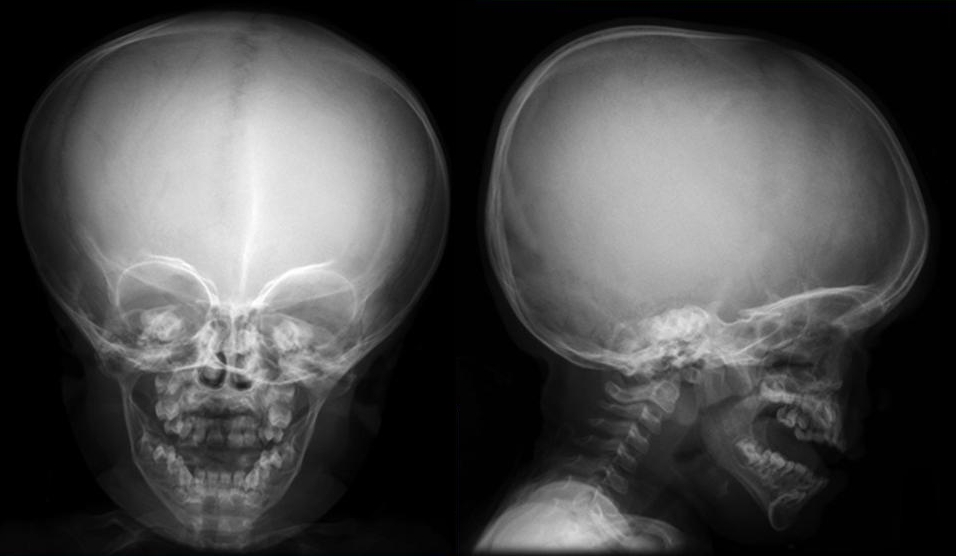

Если новорожденному требуется анализ на ахондроплазию, его должен осмотреть нейрохирург. Изменения также могут быть видны на УЗИ. Врачи рекомендуют пройти МРТ и КТ головного мозга. Для оценки состояния носовых проходов и ЛОР-органов пациента обследует отоларинголог. В некоторых случаях может понадобиться консультация пульмонолога. Для диагностики патологии применяют рентгенографию:

- черепа;

Синдром Парро-Мари характеризуется аномалиями лицевого скелета, возникающими из-за неправильного формирования костей. У пациентов с этим заболеванием глаза расположены широко и глубоко в орбитах, а внутренние уголки глаз могут иметь дополнительные складки.

Признаки патологии можно определить по характерной форме носа, который выглядит как седло — сплющенный и широкий в верхней части. Язык у таких пациентов имеет грубую текстуру, а небо — высокое. Конечности у больных с ахондроплазией укорочены пропорционально, также у них наблюдаются широкие и короткие стопы.